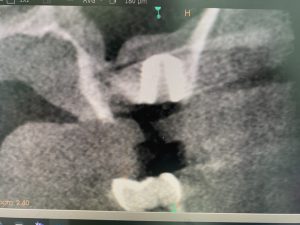

添付画像の通り、裾野も拡く5ミリ位挙上出来バッチリ

白色に見えるのは、塊のコラーゲン製剤

挙上空間スペースは自家骨に置換されるので、より安定性増し